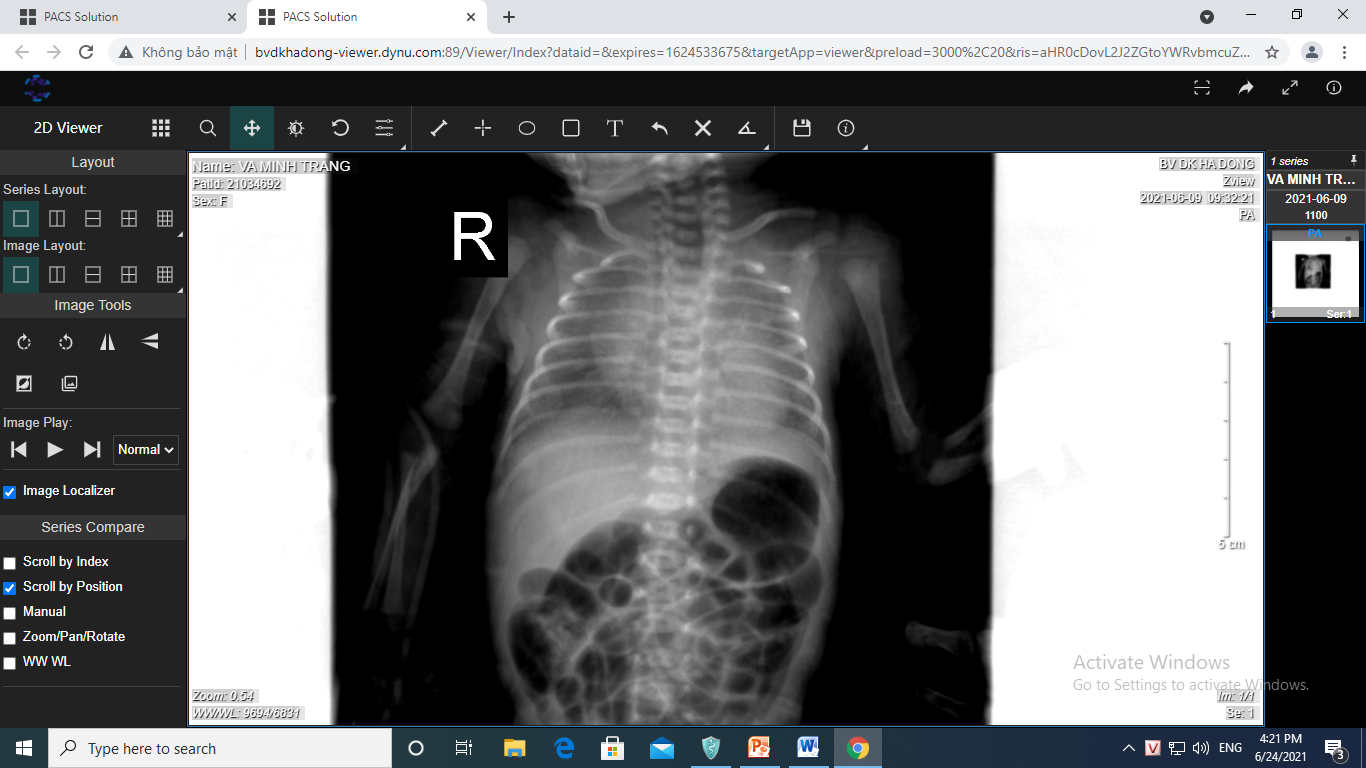

Trước bơm surfactant bằng phương pháp insure cho ca bệnh 30 tuần nặng 1200gr